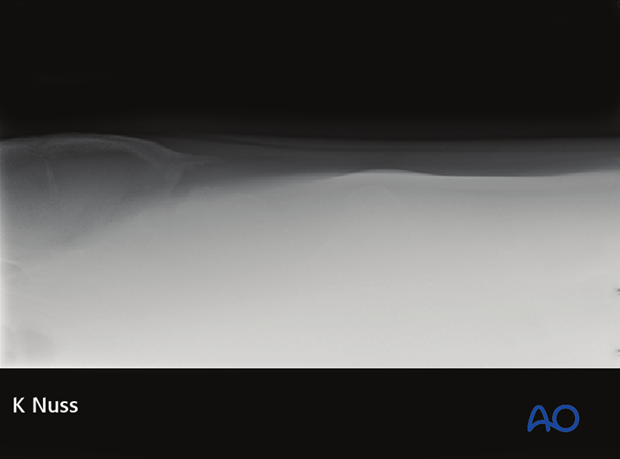

Radiographs:

• Fracture lines are often poorly visualized

Radiographic examination:

• Lateral radiographs

• Ventrodorsal radiographs are usually unrewarding